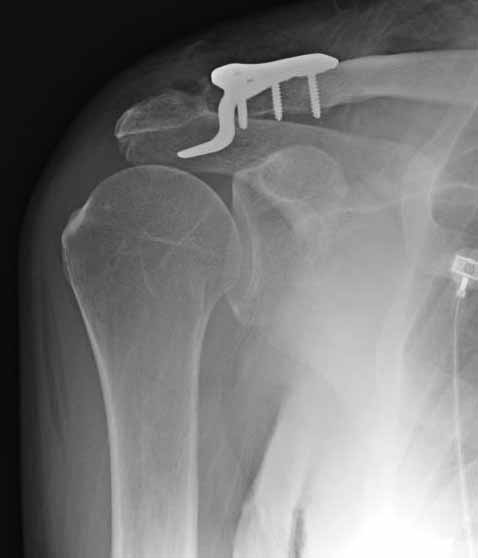

foto 4

4.JPG

14KB (14434 bytes)

|